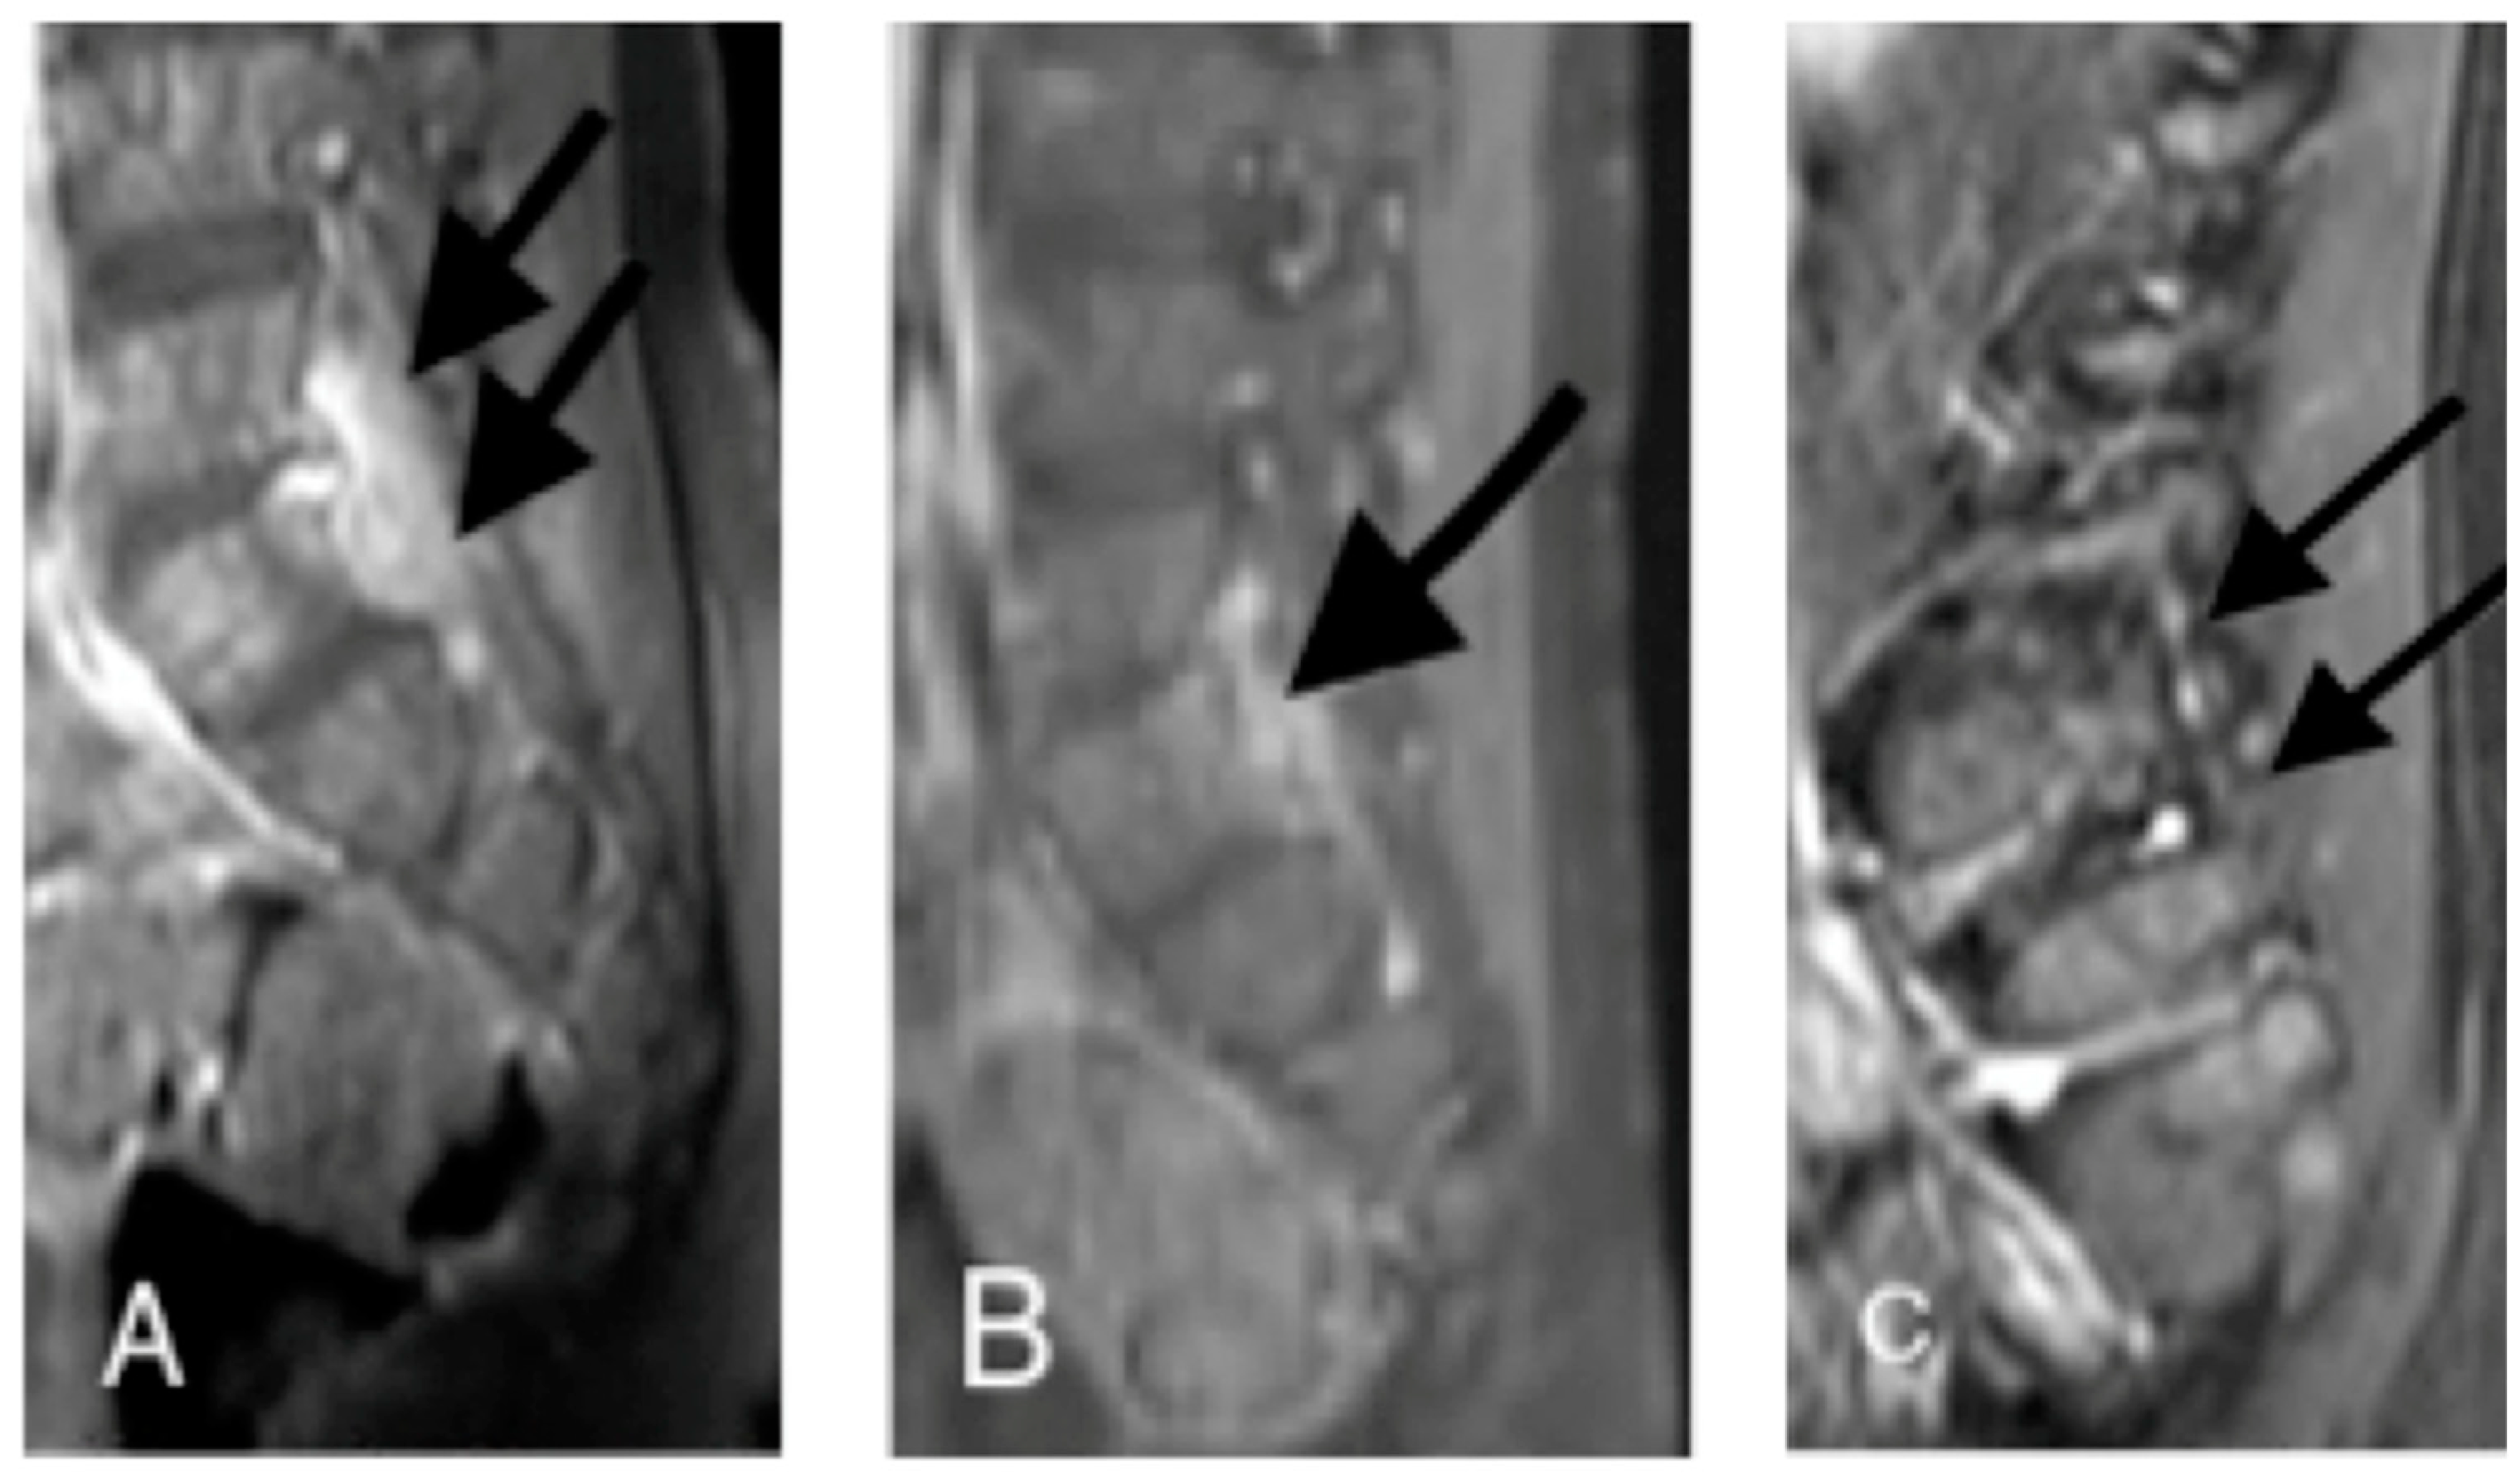

2.2. Case 2